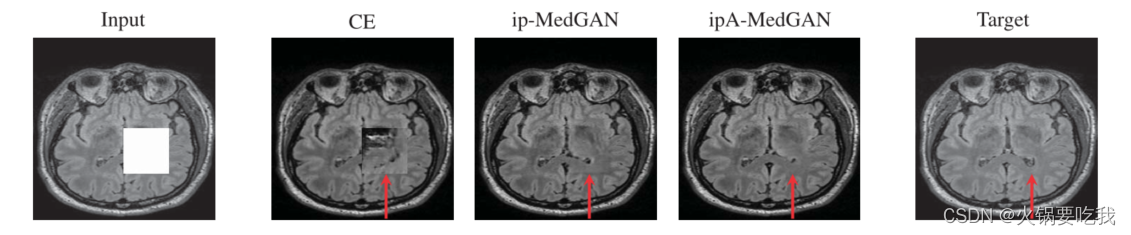

分别进行了缺失部分是矩形和不规则形状两个实验。

当缺失部分是矩形时,不管是从定性还是定量上来说,CE的结果是最差的。ipA-MedGAN的效果较好。